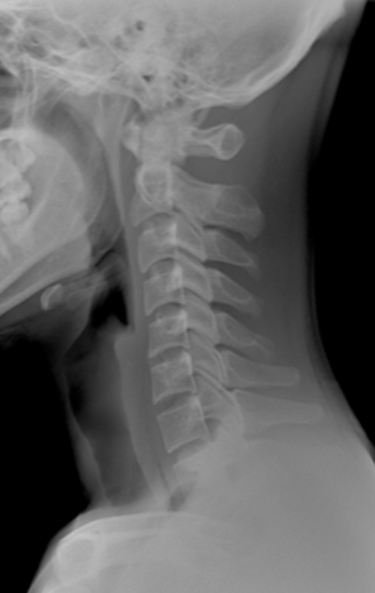

거북목 개선

경추는 정상적으로는 앞쪽이 볼록한 C자 모양을 하고 있으나,

거북목의 경우 아래쪽 목뼈는 과하게 구부러지는 방향으로 배열되고 위쪽 목뼈와 머리뼈는 머리를 젖히는 방향으로 배열되어 전체적으로

목뼈 전 만이 소실되고 머리가 숙여지지 않은 상태에서 고개가 앞으로 빠진 자세를 말합니다.

증상

- 두통이 심해지는 경우

- 목 주위와 승모근이 뻣뻣해질 경우

- 심할 경우 뒷목의 통증과 눈의 피로감을 느끼는 경우

- 목이 회전할 때 소리가 나거나 통증이 생기는 경우

- 어깨의 통증과 손, 발 저림 현상이 나타나는 경우